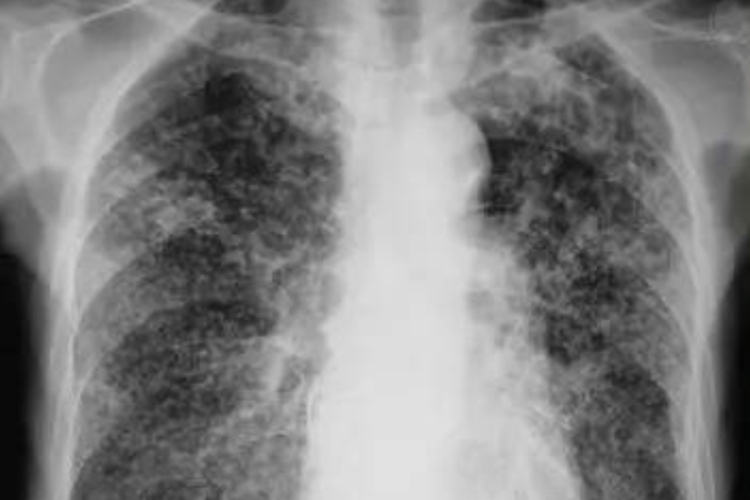

急性血行播散型肺结核:表现为两肺弥漫分布的粟粒状影,粟粒大小为1-3mm,边缘较清晰。典型表现为“三均匀”,即分布均匀、大小均匀和密度均匀。